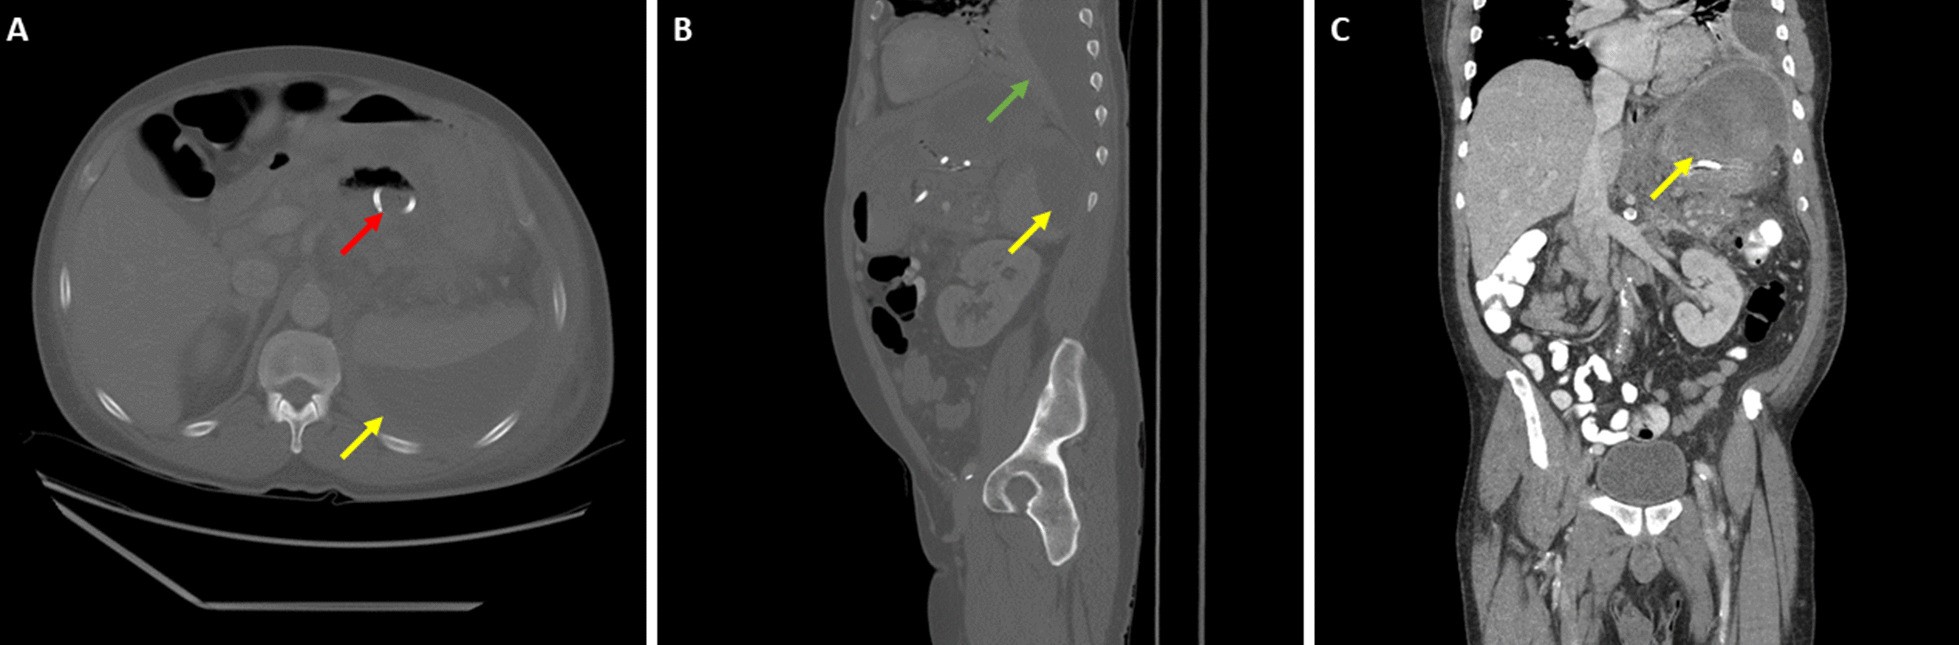

Fig. 3

From: Splenic injury following endoscopic drainage of a large pancreatic pseudocyst: a case report

Computed tomography imaging of the abdomen and pelvis with intravenous contrast of pancreatic pseudocyst and new subcapsular collection after cystogastrostomy placement. A Axial view, B sagittal view, C coronal view. Red arrow denotes cystogastrostomy tube, yellow arrows denote subcapsular collection, and green arrow denotes new left-sided pleural effusion